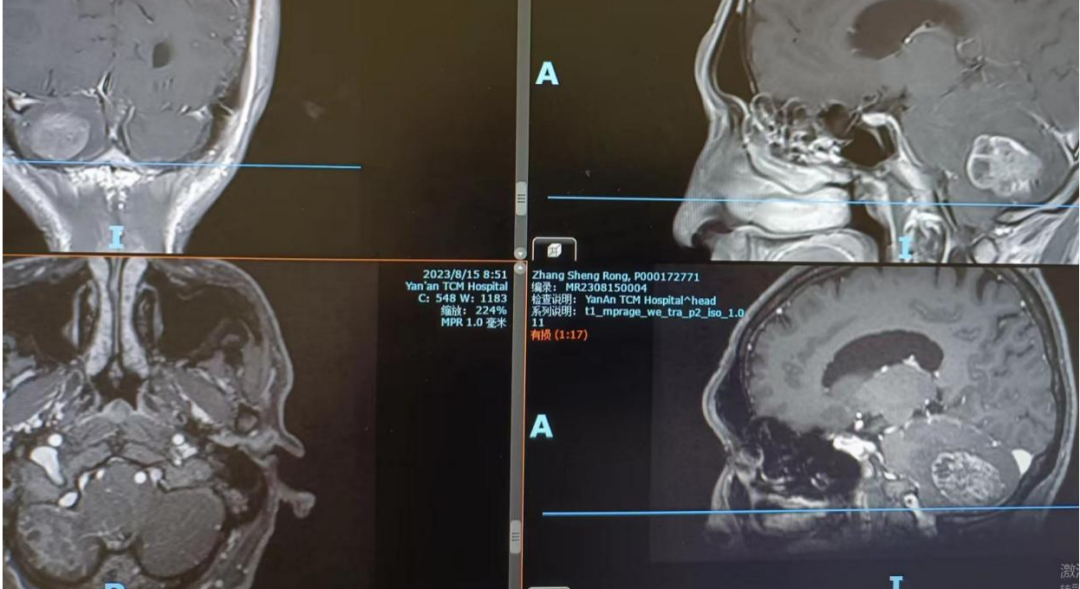

“患者张某,65岁,2年前曾行食道肿瘤切除术,近20天来头晕头痛伴恶心呕吐,检查后发现右侧小脑占位病变。”

“直径接近5cmX5cm,肿瘤周围水肿明显,四脑室受压、移位,小脑扁桃体下疝入枕骨大孔内。”

“患者系胃贲门癌术后2年,小脑右侧半球占位性病变,且四脑室受压,小脑扁桃体向椎管挤压,颅内高压明显,目前情况危急。”

术后患者麻醉苏醒后意识清楚,肢体活动无障碍。术后6小时复查,肿瘤切除完整,肿瘤占位效应解除。目前患者正在进一步观察治疗中。